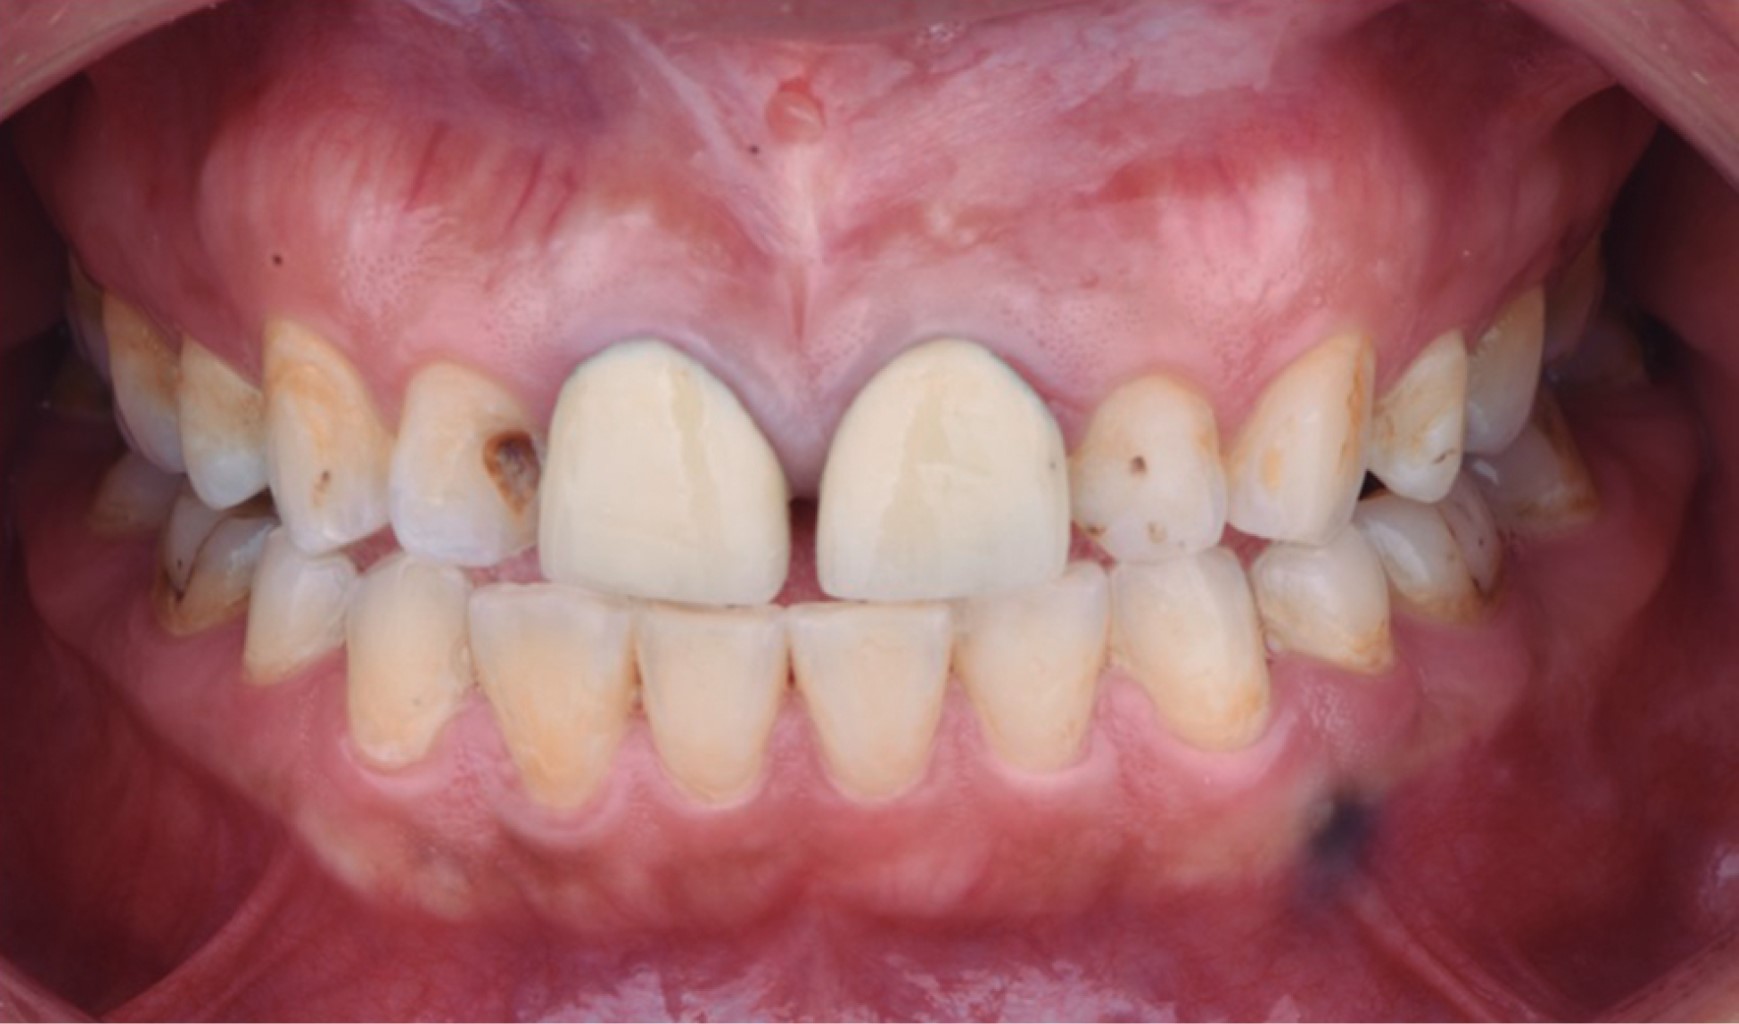

Paciente femenino de 34 años se presenta al área de Prostodoncia de la Facultad de Odontología de la Universidad Autónoma de Guadalajara (UAG) en 2017 manifestando inconformidad en cuanto a la estética de sus dientes, además, se encuentran desgastados ya que ella tenía el hábito de rechinar los dientes durante la noche. Después de completar la historia clínica y la exploración intraoral se llegó al diagnóstico de pérdida de guía anterior debido a un desgaste dental patológico sin pérdida de dimensión vertical, en combinación con lesiones cariosas y restauraciones mal ajustadas.

El plan de tratamiento requirió de un trabajo interdisciplinario en el que se indicó tratamiento de conductos y coronas de disilicato de litio (e.max, Ivoclar Vivadent) en los incisivos centrales y laterales superiores; carillas del mismo material en los caninos superiores izquierdo y derecho (Figura 1). Para iniciar el tratamiento se tomaron modelos de estudio, registro de mordida (Occlufast, Zhermack) y arco facial para montar los modelos en un articulador semiajustable (PCH-Panadent) (Figura 2). Posteriormente se realizó encerado diagnóstico para la confección de un Mock-up (Figura 3), en donde se evalúa la función de la nueva guía anterior establecida y deben ser realizadas pruebas de fonética y estética.

Una vez terminada la fase diagnóstica en donde se evalúan factores estéticos como las formas anatómicas, proporciones dentales, exposición de bordes incisales en reposo y funcionales devolviendo la guía anterior, se retiraron las coronas de los órganos dentarios (OD) 11 y 21, al igual que las lesiones cariosas de los OD 12 y 22 (Figura 4). Se realizó una interconsulta con el departamento de endodoncia y se procedió a realizar tratamiento de conductos a estos dientes. Una vez terminados los tratamientos de conductos se colocaron postes metálicos paralelos (Para-Post) en los OD 11 y 21 debido a que se necesitaba aumentar la altura del muñón protésico para retención de la restauración.10 Una vez sellados los tratamientos de conductos de las cuatro piezas se volvió a colocar el Mock-up para utilizarlo como guía de desgaste para las preparaciones dentales mínimamente invasivas (Figura 5).

Para el acondicionamiento del diente, se grabó el esmalte con ácido ortofosfórico 37% durante 20 segundos, seguido de un lavado con agua para posteriormente aplicar un adhesivo universal (Ivopen, Ivoclar). Se procedió a cementar las restauraciones con cemento Variolink Esthetic LC (Ivoclar Vivadent) fotocurándolo durante 3 segundos antes de retirar excedentes y para realizar un fotocurado final de 20 segundos por cada cara libre. Finalmente, se fotocuró sobre una capa de glicerina para eliminar la capa inhibida por oxígeno. Se puede observar un cambio estético (Figura 7) y funcional con el restablecimiento de la guía anterior (Figura 8) en comparación con la situación inicial, además se realizó un guarda oclusal con acrílico termocurado.

Figura 1